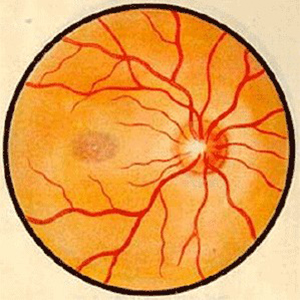

视神经病变

易游体育学术资讯:脉络膜新生血管医治 评估的思考